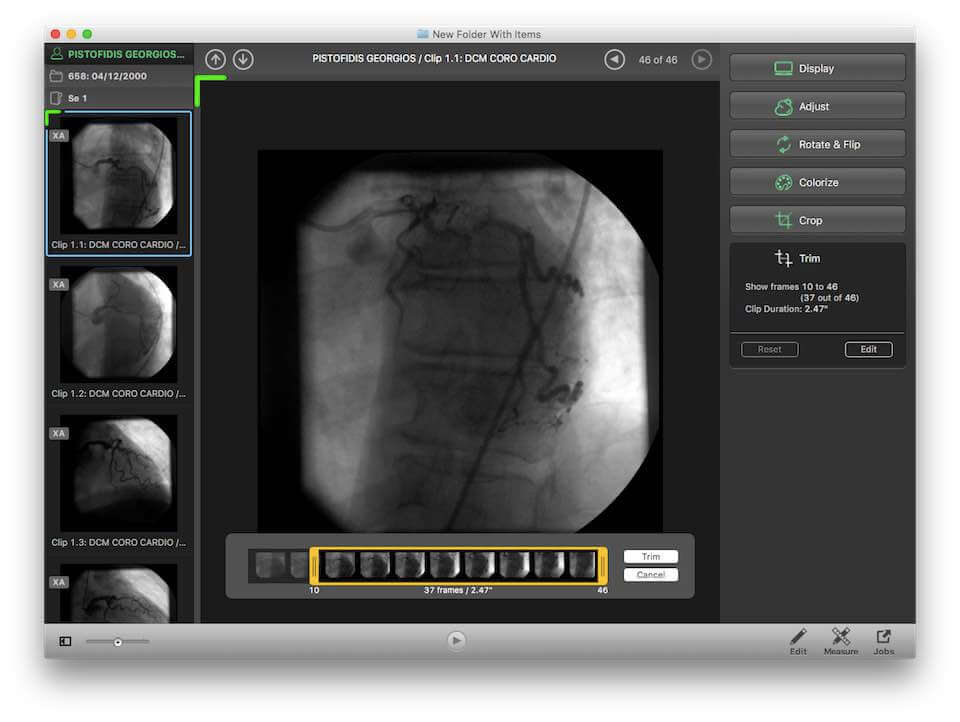

Horos is an open source DICOM viewer for Mac. It is actually the free version of an expensive DICOM viewer called Osirix MD, which is often considered to be the best DICOM viewer for Mac. It only runs on Mac OS, version 10.8 or higher. This software allows for most diagnostic techniques, including multiplanar reconstruction, maximum intensity projections, and volume rendering. It also has tools for manipulating images and making measurements.

One of the unique features of Horos is that it has a plug-in that allows uploading of images to Radiopedia, an online resource with a large number of reference cases and articles. Technical support is available through both phone and email. Horos, however, does not integrate to PACS free of cost. Cloud-based storage is available at an additional cost.